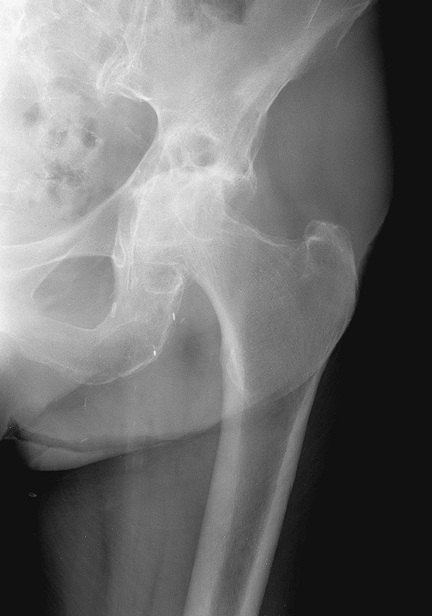

![]() |

|

Figure 3-3

Radiographic example of patient with osteoarthritis. Note the superolateral joint space narrowing, bony sclerosis, and large osteophytes. The changes are much more hypertrophic than that seen in inflammatory arthritis. |